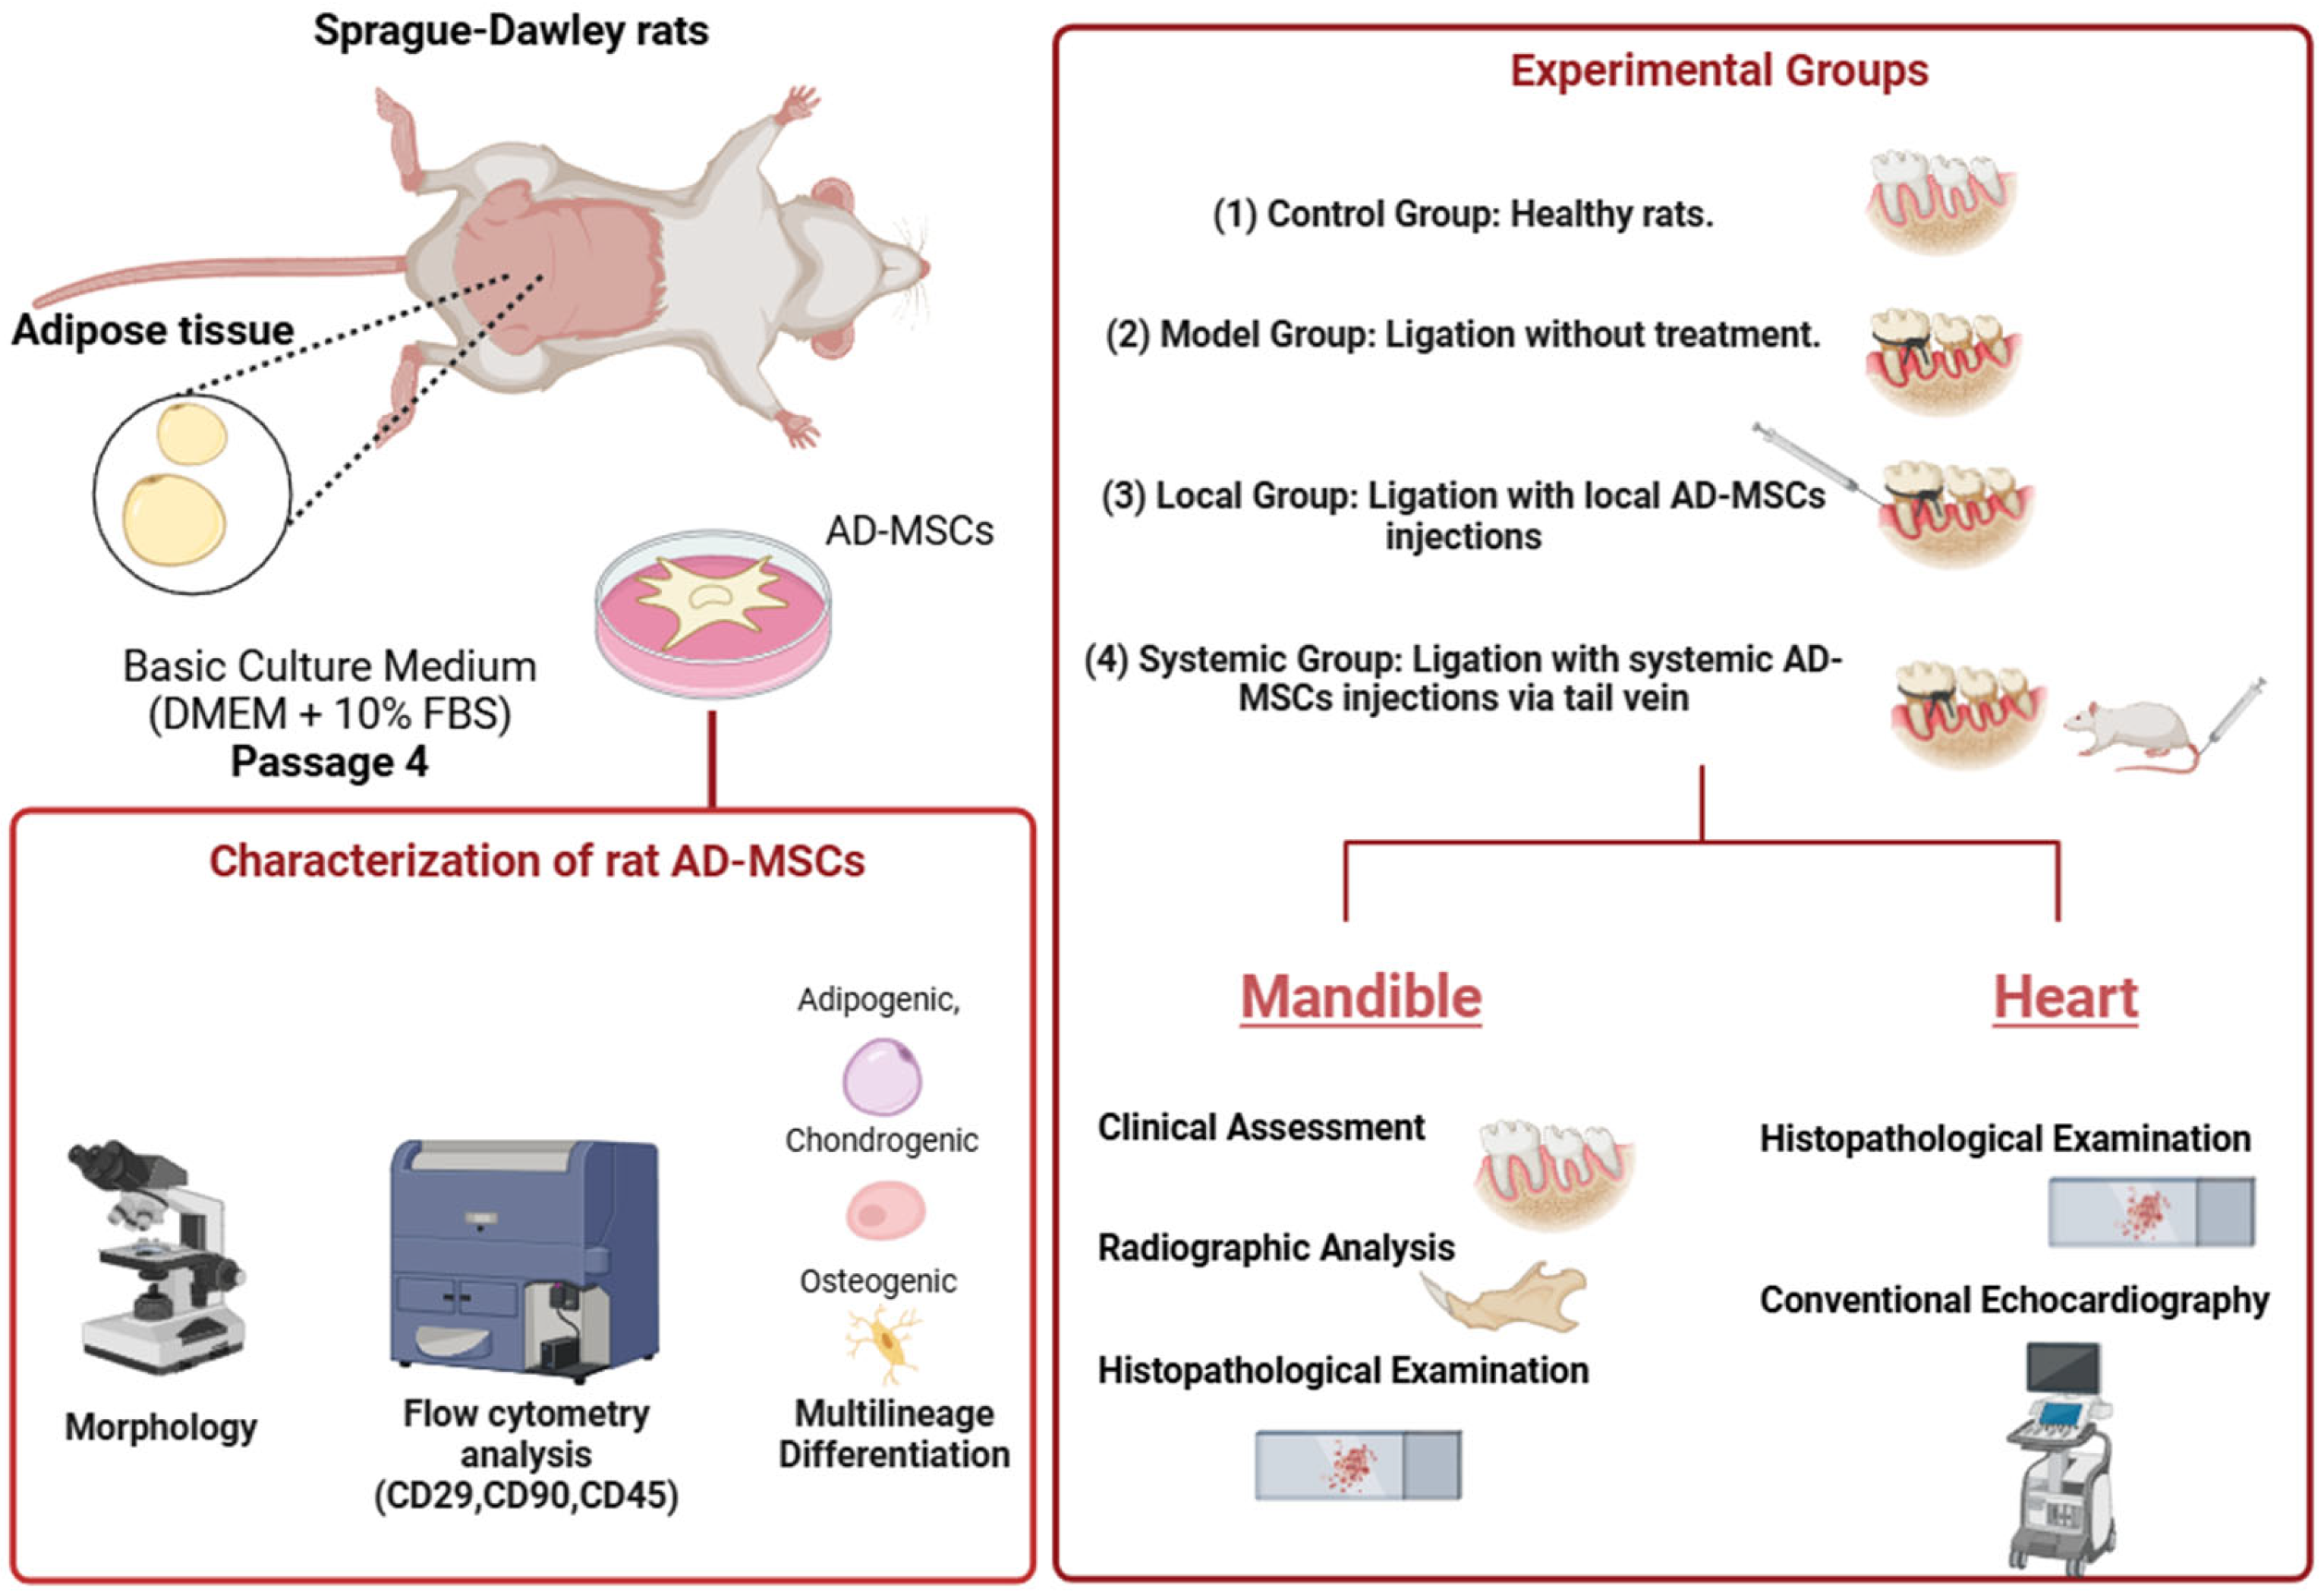

4. Materials and Methods

4.1. Animal Care and Ethical Compliance

4.2. Preparation and Culturing of AD-MSCs

4.3. Flow Cytometric Characterization of AD-MSCs

4.4. Multilineage Differentiation Assessment of AD-MSCs

4.5. Experimental Groups and Treatment Protocols

- Control Group: No ligation or AD-MSC treatment.

- Model Group: Ligation-induced periodontitis without AD-MSC treatment.

- Local Group: Ligation followed by local AD-MSC injections (1 × 106 cells) delivered supraperiosteally near the bone surface.

- Systemic Group: Ligation followed by systemic AD-MSC injections (1 × 106 cells) via the tail vein.

4.6. Clinical Assessment of Periodontal Bone Loss

4.7. Radiographic Assessment of Alveolar Bone Loss and Periodontal Bone Support

4.8. Histopathological Examination

4.8.1. Mandibular Tissues

4.8.2. Cardiac Tissues

4.9. Conventional Echocardiography